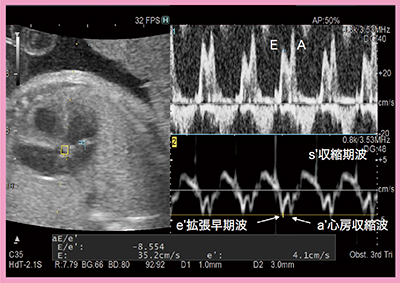

3)E/e’の計測

E/e’は,平均左房圧または肺動脈楔入圧を反映しており,成人では左心系の拡張能の指標として臨床応用されている。従来法(Single Doppler法)では,同一心拍での複数波形の測定は不可能であり,異なる心時相で測定するため誤差が生じるほか,心房細動などで心拍数が頻繁に変動する症例では正確なE/e’を算出することができない。これらの課題はDual Gate Dopplerにて解決可能であり,最近では胎児への臨床応用の可能性も検討されている。当院でのE/e’の計測結果(図5)を見ると,PW法にてE波,A波が,また,TDI法にてe’波がきれいに描出されている。現状では胎児のE/e’の正常値が設定されていないが,施設内のコントロール群で正常値を設定し,左心低形成症候群(HLHS)の胎児の右室のE/e’を比較したところ,正常値に比べてE/e’が有意に高かったとの報告がある2)。

図5 Dual Gate DopplerによるE/e’計測